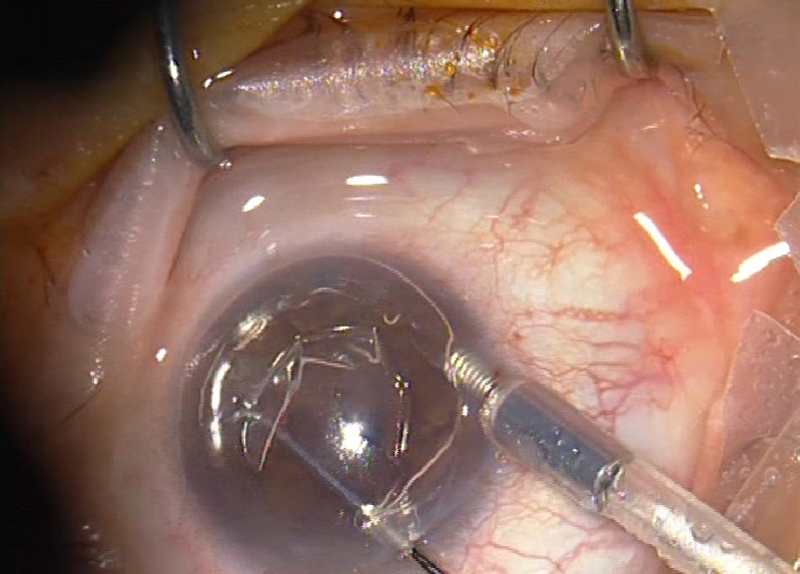

Inserción del PCT en el receptor. El primer paso consiste en una descemetorrhexis de 8.5-9.0 mm, previa realización de una facoemulsificación de cristalino e implante de LIO en ojos fáquicos (Figura 4). Además siempre se ha realizado una iridotomía a las 6 h con vitrectomo si no estaba previamente hecha con láser YAG. La lamela endotelial se ha insertado tirando de ella desde una paracentesis contralateral (técnica de pull-through) (Figura 5). La incisión principal se ha practicado de 5 mm de longitud para no comprimir demasiado el tejido a su paso. La lamela se ha depositado en el insertador de Busin (Figura 6) y la pinza de Tan se ha usado para tirar de ella. Se rellena la cámara con el 90-100% de aire y si a los 20 minutos aproximadamente de reposo en decúbito supino se observa un pequeño menisco de acuoso al poner el paciente en bipedestación no se extrae ninguna cantidad de aire de la cámara anterior (Figura 7).

Figura 5. Inserción en la cámara anterior mediante técnica de pull-through. Con la pinza de Tan se tira del tejido desde una paracentesis contralateral.

Figura 6. El tejido es insertado dentro del insertador de Busin justo antes de la inserción. Previamente se ha trepanado al diámetro requerido (8.0-8.50 mm).